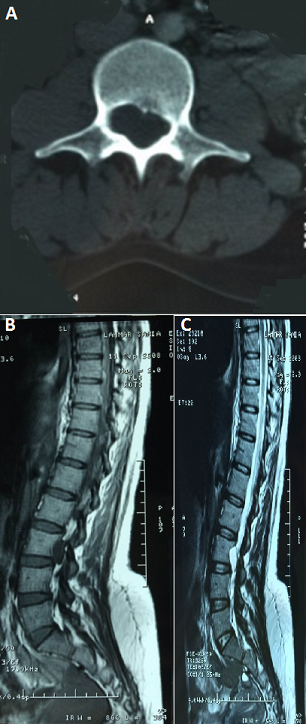

Le kyste arachnoïdien est un diverticule méningé communiquant dans la majorité des cas avec les espaces sous-arachnoïdiens. Il peut avoir une origine congénitale ou traumatique. La présentation clinique dépend de la taille et de la localisation de la formation kystique. Nous rapportons le cas d'une patiente SH âgée de 36 ans, sans antécédents pathologiques particuliers, elle a consulté pour des lombalgies chroniques mécaniques non impulsives évoluant depuis 10 ans et s'exacerbant surtout en position debout. L'examen a trouvé un trouble statique du rachis: une hypercyphose dorsale compensée par une hyper lordose lombaire avec des flèches vertébrales au niveau de C7:100mm, D8: 0mm, L3: 80mm, S: 0mm. Il n'existe pas de syndrome rachidien, le reste de l'examen clinique est sans particularités. Le bilan biologique est revenu normal, la radiographie standard n'a montré que le trouble statique dans le plan sagittal. Devant la non amélioration par un traitement médical et un protocole de rééducation adapté un scanner lombaire a été demandé. L'IRM a conclu à la présence à l'étage L3-L4 d'une masse intracanalaire qui élargit le foramen intervertébral sans signe de compression du fourreau dural en rapport avec un kyste arachnoïdien. Ainsi, la patiente a été adressée en neurochirurgie.